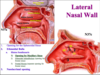

What is the major arterial supply to the posterior 2/3 of the nasal cavity?

Sphenopalatine artery, through its 2 major branches:

1) Posterior Lateral Nasal artery

2) Posterior Septal artery